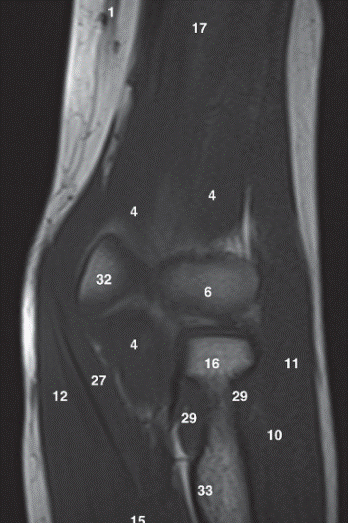

13

Q

Label 5,12,13,37,38

A

5=Capitate

12-Hamate

13=Hook of Hamate

37=Trapezium

38=Trapezoid